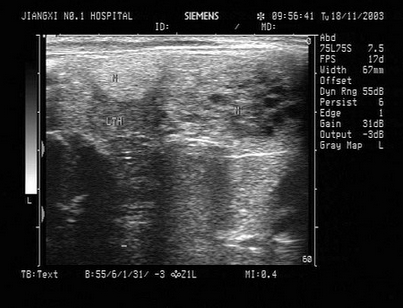

57、单项选择题

某患者高热,肾区疼痛,肾脏超声声像图如下,最可能的诊断为()

A.肾囊肿

B.急性肾炎

C.脓肾

D.肾癌

E.肾结核